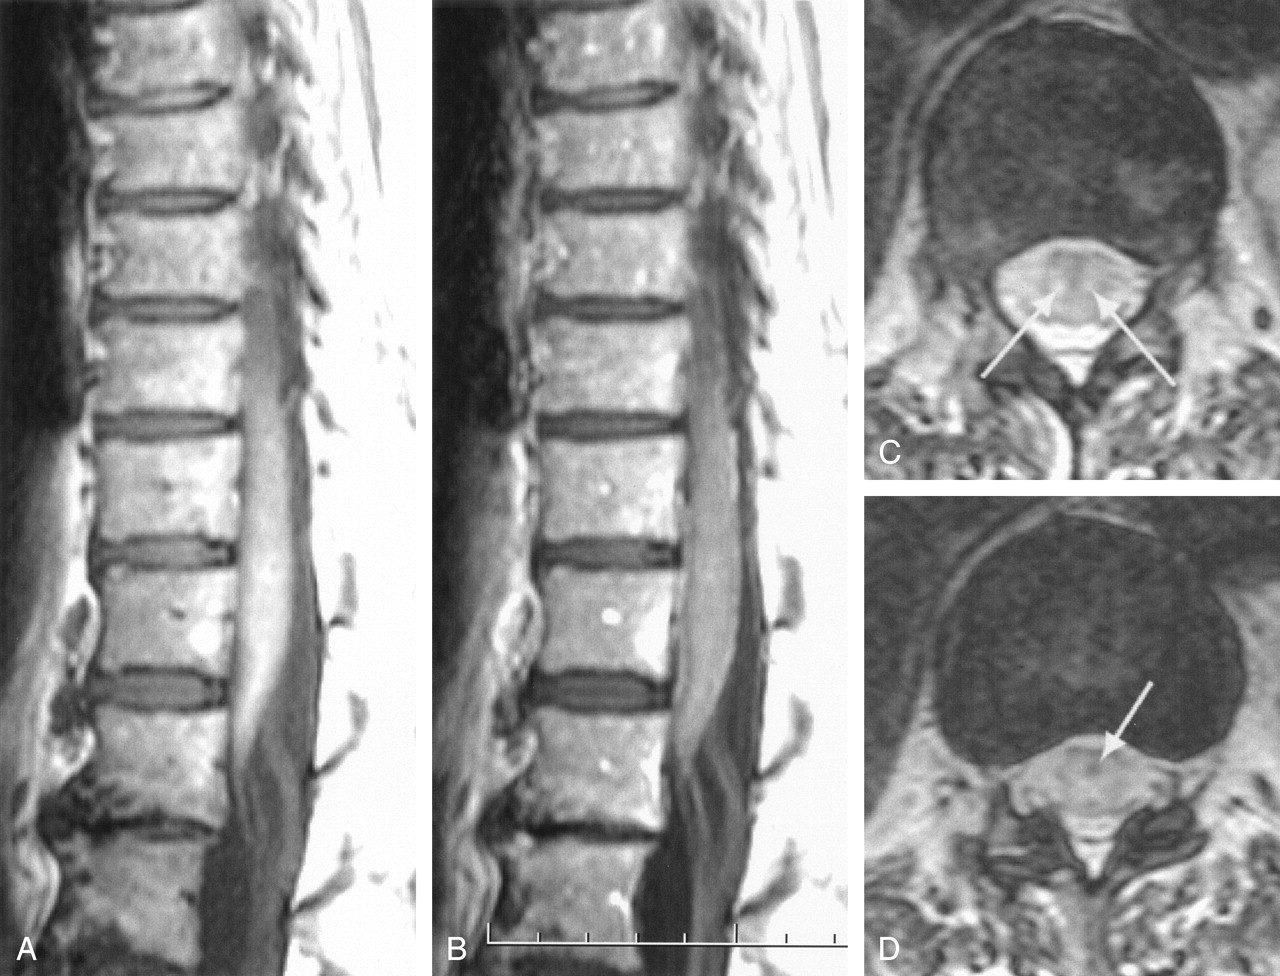

Plantar reflexes were unobtainable. A sensory level for pain and temperature was present from the L4 to the S5 level, mainly on the left side. The patient also suffered from urinary retention and fecal incontinence. MR imaging examination on admission demonstrated thin linear ependymal contrast enhancement on postcontrast T1-weighted images and slightly increased T2 signal intensity of the conus terminalis. An incidental hydrosyringomyelitic (HSM) cavity extending from Th7-Th8 to Th11 was present (Fig 1). Findings on CSF examination were normal except for a slightly elevated protein concentration at 58 mg/dL (normal range, 15–45 mg/dL). Because the patient’s clinical status failed to improve, both examinations were repeated 5 days later.

MR imaging examination on admission.

A, Postcontrast midsagittal T1-weighted spin-echo image shows caudal extremity of the HSM cavity and thin linear enhancement of the epithelial lining of the ependymal canal within the conus. Cord parenchyma does not enhance.

B, Midsagittal T2-weighted fast spin-echo (FSE) image of the lumbosacral spine shows thin longitudinal central conal hyperintensity corresponding to enhancing linear area in panel A and slightly increased signal intensity of the conus. Disk protrusions (thin arrows), chronic osteoarthritic changes (paired arrows), and small Schmorl nodes (thick arrow) are present.

C, Midsagittal T2-weighted FSE image of the cervicodorsal segment shows upward extension of the incident HSM cavity to Th7-Th8. The cord cephalad to this level is normal.

D, Transverse T2-weighted FSE image at the T12 level shows slightly increased signal intensity of the conal parenchyma, mainly on the right side (thicker arrow). Ependymal canal is visible (thinner arrow).